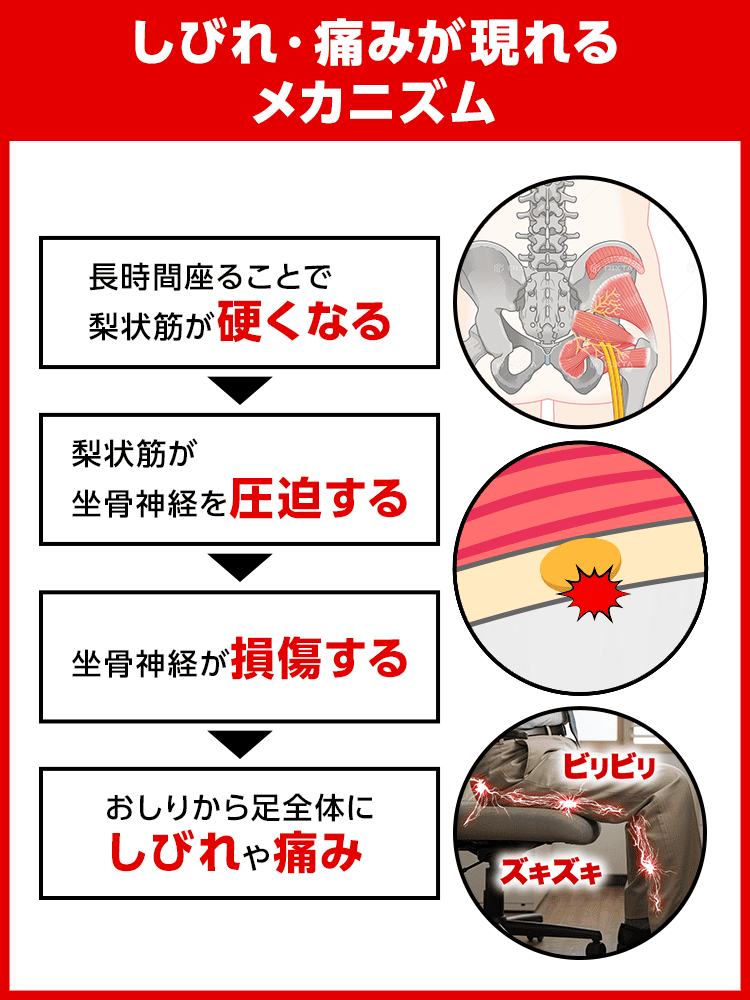

こんな痛みやしびれの原因は

梨状筋(りじょうきん)というおしりの奥の筋肉が硬くなること。

というのも

梨状筋のそばには坐骨神経が通っており、

梨状筋が硬くなると坐骨神経が圧迫されて傷ついてしまいます。

そして坐骨神経はおしり〜足先まで伸びているため、

損傷すると様々な箇所にしびれや痛みが現れるんです…

つまり、

これがしびれや痛みのメカニズム!